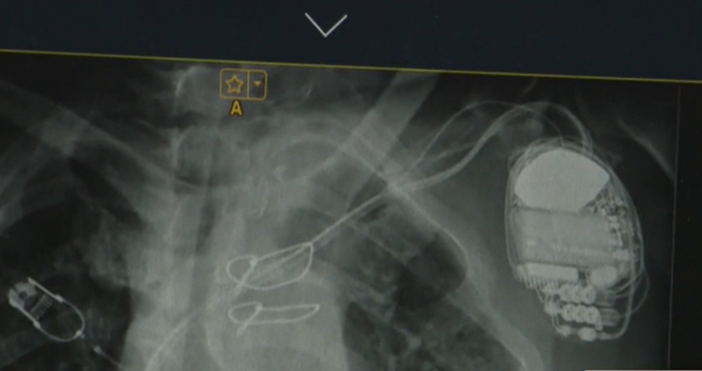

... екип от лекари на УМБАЛ "Света Екатерина" извърши първата по рода си в България операция от този тип. Пациентът вече е трансплантиран и е добре.

За втори път у нас поставиха две изкуствени сърца на